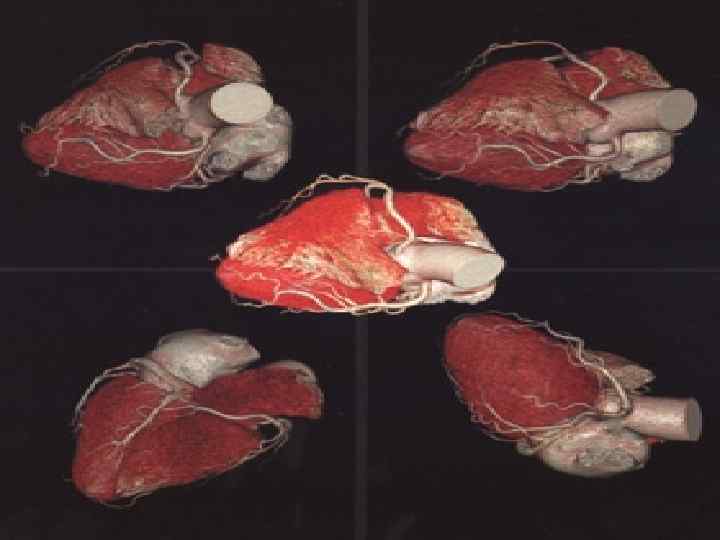

МАГНИТНО-РЕЗОНАНСНАЯ ТОМОГРАФИЯ(МРТ) СЕРДЦА Магниттi - резонанстық томография орталық жүйке жүйесi, омыртқаның ауруларын диагностика арқылы зерттеудiң аналог болмайтын сирек кездесетiн iс жүзiнде бұлшық еттiк болып табылады - буын жүйе және iшкi органдардың қатары. Сутектiң протондарын адамның организмінде резонанста негiзделгеннiң зерттеу онының магниттi алаңына үй-жайда. Сәулелiк жүктеменiң жоқтығы емделушi үшiн магниттi - резонанстық томография қауiпсiз iстейдi және бiрнеше тексерулер қатар өткiзуге мүмкiндiк бередi

Жағдайларды қатарда көк тамырiшiлiк қарама-қарсы күшейтуi бар зерттеудiң өткiзу МРТ диагностикалық қажеттiлiгi пайда болады. Зерттеудiң мәлiметтерi дәрiгер МРТ емдеушi дәрiгер немесе бағыт бойымен тек қана жүргiзiледi. Қарама-қарсы препараттың енгiзуi қосымша реакциялардың ең төменгi тәуекелiнде болады. Сiзгеге контрасты заттың енгiзуi жағдайда сауалнаманы толтыруға ұсыныс жасайды - қарама-қарсы препараттың көктамырiшiлiк енгiзуiне ақпараттық келiсiмнiң парағы.

Зерттеуге абсолюттiк қарсы көрсетулермен жатады: ми ыдыстарында кардиостимулятордың бар болуы, ферромагниттi имплантовтары, клипс. Зерттеу бұл жағдайдалардағы қатал қарсы көрсеткен. (зерттеу өткiр қажеттiлiктiң жанында жүргiзiле алады) салыстырмалы қарсы көрсетулерге металлдың мазмұнымен жүктiлiктiң бiрiншi триместрi, жүректiң жасанды клапандары, орнын толтырмалған жүрек мүкiсi, инсулин сорғылары, импланты, металлдық брекетыларда әкетедi. Сонымен бiрге темiрi бар бояуларды қолданумен салыстырмалы қарсы көрсетулер сияқты қарау керек болуға iстеп шығылған татуировкалар.